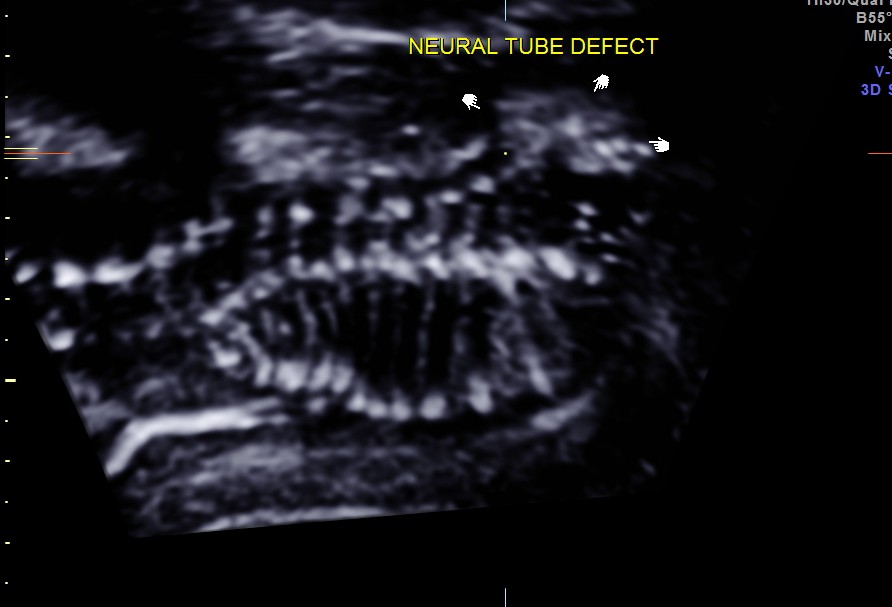

The fetal head was in the upper pole , with the spine posterior in location throughout the study.The spine was studied with great difficulty . This was a flipped image showing a neural tube defect.- lumbar meningo myelocele.